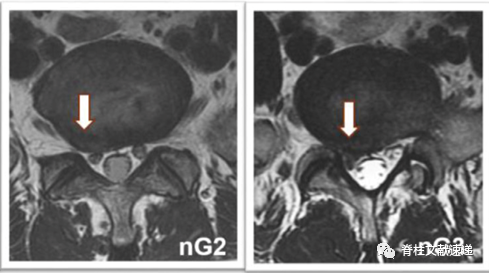

1级:椎间盘与神经根接触但未受压(nG1),或硬膜囊受压<椎管的1/3(dG1);

2级:神经根受压移位(nG2),或硬膜囊受压>1/3而<1/2(dG2)。

行髓核摘除术时,若无症状椎间盘突出为G2程度的神经根受压,再手术率较高;若为G2程度的硬膜囊受压,再手术率无明显提高。这对初次手术时髓核摘除术减压节段的选择提供了一定参考。